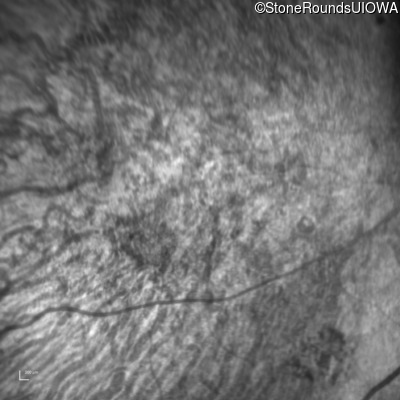

This 41 year old man first came to medical attention at age 18 months when exotropia and amblyopia of his right eye were discovered. At age 11 vitreous strands and retinal vascular sheathing were seen. He has had poor night vision and constricted visual fields since his late teens. Later, at age 44 a traction retinal detachment was noted in his left eye and was treated with a scleral buckle.

Age at visit: 41 years